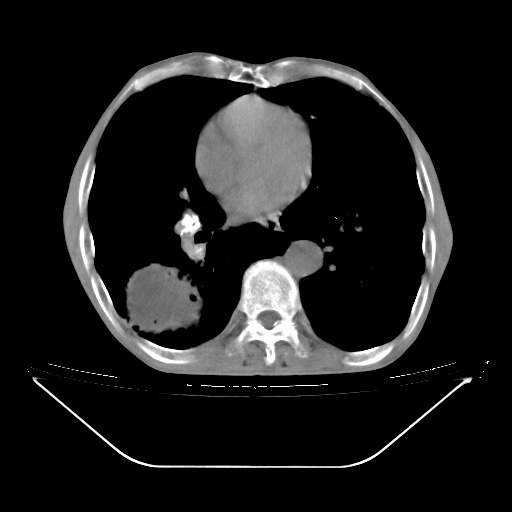

以下是引用zsl6918在2008-8-25 21:55:00的发言:[br]符合右肺周围性肺癌并肺内转移,左肺结核球。双肺肺气肿。腰椎附件转移。

以下是引用随光逐影在2008-8-25 22:03:00的发言:[br]1)考虑右肺下叶周围性肺癌并肺内转移,腰椎附件转移。2)左上肺结核(结核球形成)。3)双肺肺气肿(多发肺大泡形成)。4)双肺门区及纵隔内多发淋巴结钙化。